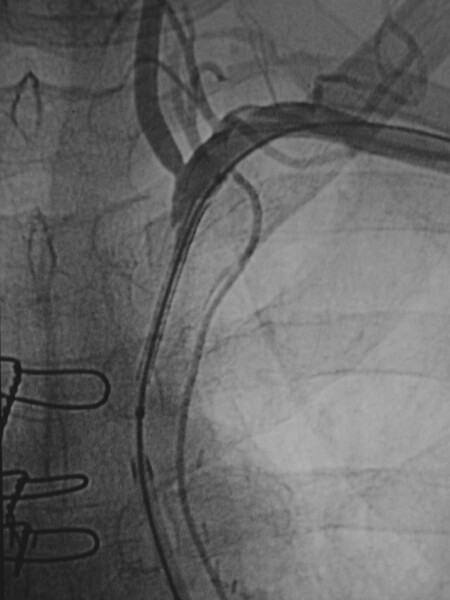

Lagte image from a thoracic aortogram demonstrating reconstitution of the left subclavian via retrograde flow in the left vertebral artery. -

Single image showing the upper extremity catheter access enabled guidewire passage across the occlusion. A snare was placed from common femoral artery access and used to capture the wire, enabling "through and through" access across the occlusion. -